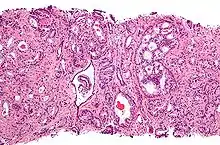

![]() Gleason grade — Lower grades are associated with small, closely packed glands. Cells spread out and lose glandular architecture as grade increases. Gleason score is calculated from grade as described in the text. |

A pathologist microscopically examines the biopsy specimen for certain "Gleason" patterns. These Gleason patterns are associated with the following features:

- Pattern 1 - The cancerous prostate closely resembles normal prostate tissue. The glands are small, well-formed, and closely packed. This corresponds to a well differentiated carcinoma.

- Pattern 2 - The tissue still has well-formed glands, but they are larger and have more tissue between them, implying that the stroma has increased. This also corresponds to a moderately differentiated carcinoma.

- Pattern 3 - The tissue still has recognizable glands, but the cells are darker. At high magnification, some of these cells have left the glands and are beginning to invade the surrounding tissue or having an infiltrative pattern. This corresponds to a moderately differentiated carcinoma.

- Pattern 4 - The tissue has few recognizable glands. Many cells are invading the surrounding tissue in neoplastic clumps. This corresponds to a poorly differentiated carcinoma.

- Pattern 5 - The tissue does not have any or only a few recognizable glands. There are often just sheets of cells throughout the surrounding tissue. This corresponds to an anaplastic carcinoma.

In the present form of the Gleason system, prostate cancer of Gleason patterns 1 and 2 are rarely seen. Gleason pattern 3 is by far the most common.

The Gleason grade is based on tissue architectural patterns rather than purely cytological changes. These tissue patterns are classified into 5 grades, numbered 1 though 5. Lower numbers indicate more differentiation, with pattern 5 being the least differentiated.[4][7] Differentiation is the degree to which the tissue, in this case the tumor, resembles native tissue. Greater resemblance (lower grade) is typically associated with a better prognosis.)